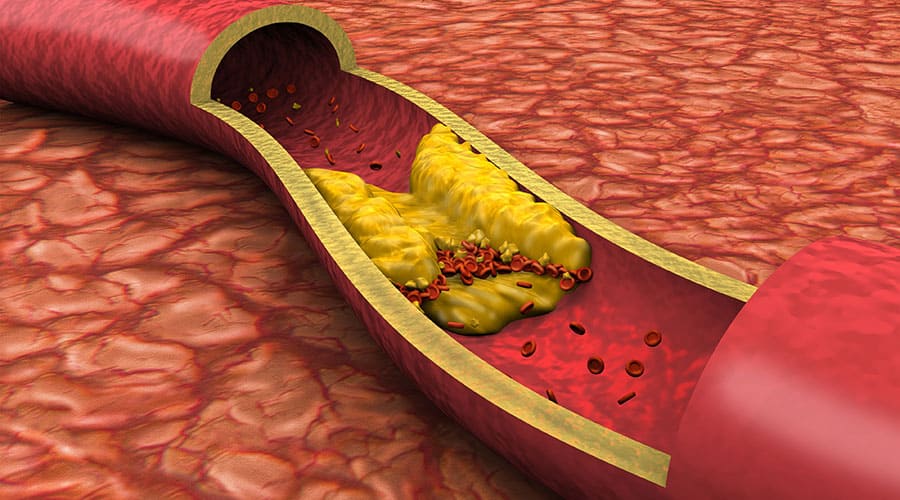

Deep Vein Thrombosis

Understanding the Significance of DVT When Serena Williams shielded her eyes from the glare of a setting sun…